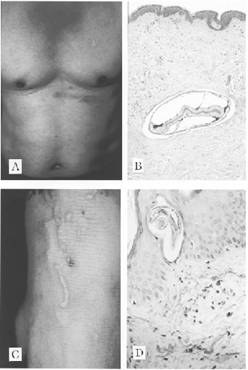

Aguirre Errastivà cs (1981)tại Tây Ban Nha báo cáo nhiễm trùng bởi F. hepatica có tần suất đang gia tăng. Qua giai đoạn 5 năm, các tác giả đã nghiên cứu có 25 trường hợp bị SLGL loài F. hepatica, tất cả trong số chúng được chẩn đoán thông qua xét nghiệm trứng trong phân hoặc trong dịch tá tràng. Trong 2 ca, vị trí nhiễm trùng lạc chỗ của ký sinh trùng cho ra các đặc điểm lâm sàng không bình thường. Trường hợp đầu tiên trình bày là giai đoạn trong gan cả vị trí da và vị trí mào tinh hoàn với một hình ảnh mô bệnh học tương tự với tổn thương tại gan. Liên quan đến mào tinh hoàn, không như trích dẫn trước đây trong y văn, thì trường hợp này lại tăng túi nước (hydrocele). Trường hợp thứ 2 trình bày với các dấu hiệu có liên quan đến hệ thần kinh trung ương và tăng bạch cầu ái toan trong dịch não tủy. Thuốc dehydroemetine có hiệu quả trong cả tất cả bệnh nhân, gồm cả những trường hợp lạc chỗ. Theo đó, một con sán trưởng thành Fasciola sp., nhưng không có tuyến noãn hoàng và phẩu tích tử cung từ thành trước của bụng một phụ nữ 32 tuổi Hàn Quốc(Chang và cs., 1991). Đây là ca bệnh đầu tiên nhiễm trùng ngoài ổ bụng được ghi nhận tại Hàn Quốc. Sán nằm ở vị trí cơ trơn phía trước kèm theo phản ứng mô hạt.L.T. Xuan và cs. (2005) tại Việt Nam đã báo cáo ca bệnh đầu tiên của SLGL ở vùng da niêm, khi chú ý đến vết di chuyển bên hạ sườn (P) của một bênh nhân nữ 40 tuổi Lấy dịch tiết từ cuối túi nước của đường rắn bò cho thấy dịch có màu nâu sáng, một con sán Fasciola sp. chưa trưởng thành đang sống, họ cho biết các triệu chứng lâm sàng giống như một hội chứng ấu trùng di chuyển.

El Ghawabi và cs. (1978) báo cáo một trường hợp nhiễm lạc chỗ. Một đứa trẻ bị abces cơ mắc cá (T). Phẩu tích ra khối abces cho thấy nhiều sán dẹt bên trong. Xét nghiệm mô hạt và kiểm tra test da cho thấy hình ảnh là con sán F. gigantica chưa trưởng thành. Huỳnh Hồng Quang và Nguyễn Văn Khá (2007) báo cáo một ca bệnh SLGL lạc chỗ ở cơ thẳng bụng bên (P) của một phụ nữ 39 tuổi sống tại Vũng Tàu, tiền sử trước đó 2 tháng có bị abces gan do SLGL lớn được điều trị khỏi bằng thuốc TCBZ, hiện nay có triệu chứng ngứa và ban trườn nhiều đợt tại vị trí cơ thẳng bụng, cứ vài ngày lại nổ gồ lên, đỏ da và ngứa nhiều, siêu âm phát hiện hình ảnh abces cơ do SLGL, xét nghiệm FasELISA dương tính hiệu giá 1/6400 và bạch cầu ái toan tăng lên 33.4%, điều trị khỏi bằng thuốc TCBZ liều 12mg/kg cân nặng, hình ảnh abces trở về bình thường sau 20 ngày và theo dõi sau 2 năm không thấy tái phát.